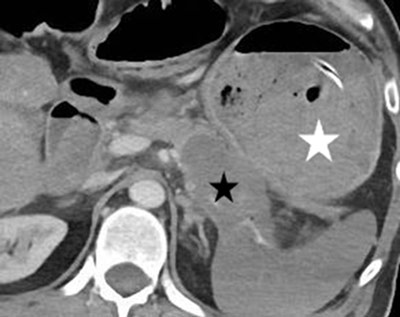

Figure 3

Axial contrast-enhanced CT image: the pancreatic neoplasm (black star) and the almost entirely clotted gastric lumen (white star).

In the wake, a CT scan was performed. A distal pancreatic tumor abutting the posterior gastric wall was demonstrated. We speculate it could be responsible for the splenic artery erosion, with the development and secondary rupture of a false aneurysm in the gastric cavity (Figure 3). The intravenous injection of contrast material did not reveal persisting blood extravasation. A new gastroscopy was performed the next day. As the stomach was no longer filled with blood, a posterior subcardial perforation was discovered, and biopsies were performed on its margins. Histological examination revealed invasive pancreatic ductal adenocarcinoma.